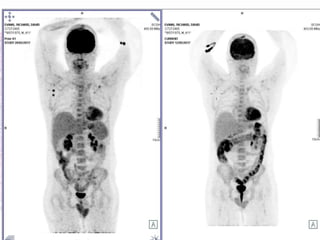

• Six months later- PET detected recurrence.

• Enrolled in Keynote-006 trial- 24 months of

pembrolizumab completed Jan 2016- complete

response

• Second course phase for recurrence- May 2016-

Aug 2016

• PD identified September 2016

• Ipilimumab commenced October 2016 - x 4

doses